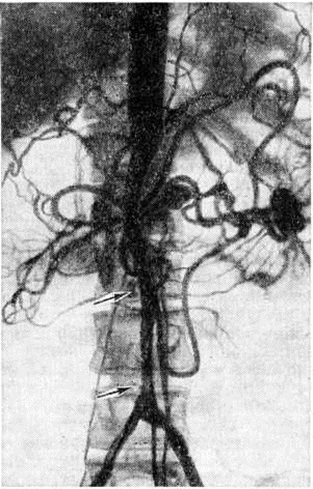

Топическую картину поражения можно установить пробой изотопной и рентгеноконтрастной ангиографии. Изотопная ангиография (смотри полный свод знаний) осуществляется пробой внутривенного введения технеция 99-м. Из методов рентгеноконтрастного исследования предпочтение следует отдать транслюмбальной пункционной аортографии (смотри полный свод знаний), при которой возможно получить изображение не только аорты, но и дистального сосудистого русла конечностей. Именно аортография выявляет локализацию и протяжённость поражения (рисунок 4—6), однако её следует проводить только при решении вопроса об оперативном лечении больного.